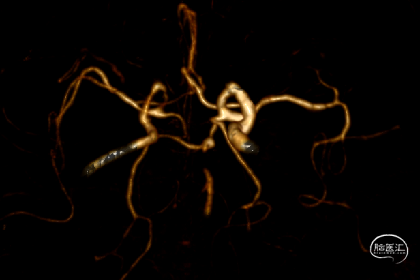

急诊头颅CT+CTA:陈旧性脑梗塞,基底动脉中段未显影,右侧椎开口狭窄。

入院头颅CTA:右侧椎开口重度狭窄,胚胎型大脑后动脉供血基底动脉上段。

基底动脉造影:基底动脉显影,中段充盈缺损,可见线性通路,远端血流mTICI2a级,考虑基底动脉血栓。

复查造影:基底动脉及远端血流mTICI 3级。

右侧锁骨下动脉造影:右侧椎动脉开口重度狭窄,狭窄率约90%,右侧椎动脉V4未显影,PICA显影可。

复查造影:椎动脉支架固定在位,v4以远显影。